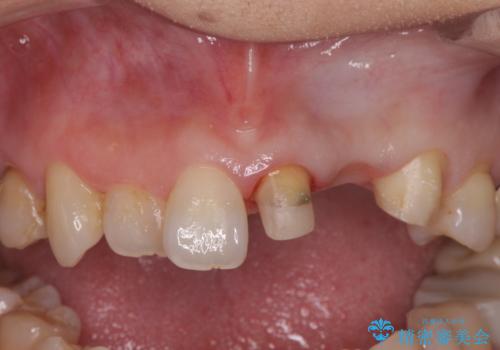

- 前歯がクラグラして噛めないことの改善を求めて来院されました。

X線撮影や歯周組織検査から、クラウン下の虫歯の再発や歯の破折が疑われる状況でした。

左上2は、クラウン メタルコアの除去を行ったところ虫歯の再発や亀裂を認め、長期的な予後の期待が難しいことから抜歯を行い

ブリッジで審美性の回復を行っていく運びとなりました。